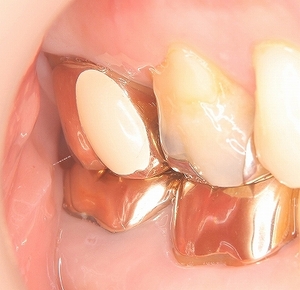

ヘミセクションの際に自分がレジンコア作るべきだったと反省。。。

仮歯を入れて経過を見て行き

ようやく1年、骨もしっかり戻ってきてくれています。

この後、クラウンは弱目の材料で作っていこうと計画しています。